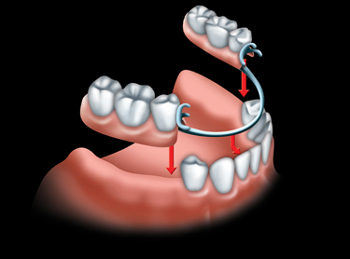

Partial dentures are also called "removable partial denture prostheses"; or "partials." They may be used when nearby teeth are not strong enough to hold a bridge, or when more than just a few teeth are missing. Partial dentures are made up of one or more artificial teeth held in place by clasps that fit onto nearby natural teeth. You can take the partial denture out yourself, for cleaning and at night.

A partial denture